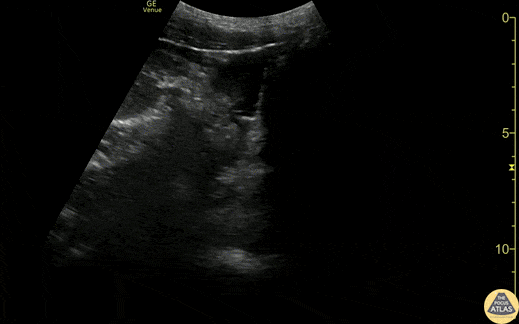

Trauma - Suprapubic +FAST from GSW

20s M presented as a walk in after sustaining a GSW to the hip. He was initially hemodynamically unstable, however responded well to transfusion of blood products and vitals normalized. FAST exam of the suprapubic/pelvic area is shown here, with heterogenous free fluid seen best in the sagittal view. FAST was also positive in the RUQ and LUQ. Plain films demonstrated a retained missile in the abdomen. As he was hemodynamically stable, CT of the abdomen and pelvis was obtained, showing hemoperitoneum and free air concerning for bowel and vascular injury. The patient was taken emergently to the OR, where exploratory laparotomy demonstrated a pelvic hematoma and hemoperitoneum from an iliac vein injury, as well as multiple areas of small bowel injury. His injuries were repaired, he recovered well, and was discharged within days of his injury. Dr. Ian Eisenhauer, PGY1 Denver Health Residency in Emergency Medicine